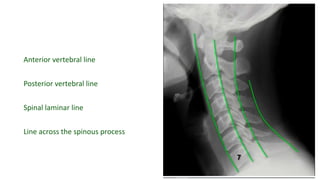

Anterior vertebral line

Posterior vertebral line

Spinal laminar line

Line across the spinous process

• #23 Ant vert body line Post vert body line Spinal laminar line Line across the spinous process